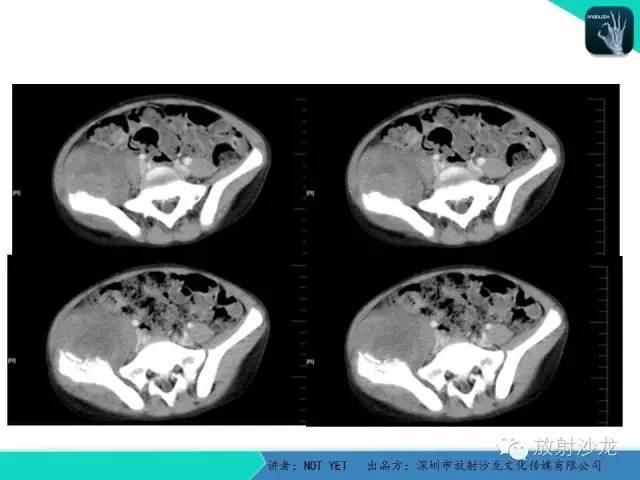

【病例】右侧髂骨Ewing肉瘤1例CT影像表现